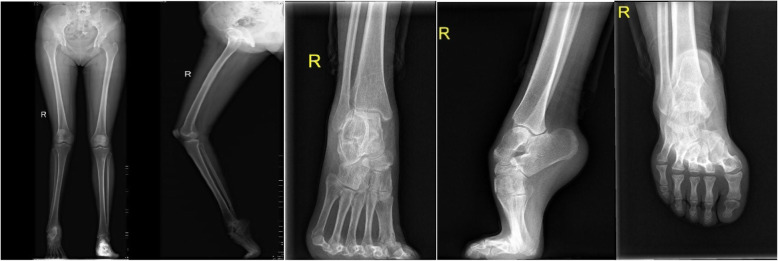

A complete radiographic evaluation is important. Weight-bearing ankle and foot radiographs including AP view, lateral view, long axis view of calcaneous are essential. The full-length X-ray of both lower limbs in the standing position is also needed (Fig. 2). A weight-bearing AP view of the ankle and foot helps to assess the condition of the ankle and whether there is rotational deformity of the foot. A weight-bearing lateral view is especially helpful. The long axes of the talus and first metatarsal create Meary’s angle. A normal measurement is 0 to 5°. The Pitch angle measures the plantar aspect of the calcaneous with the weight-bearing surface. Normal measurement is around 25°, and anything over 30° should be considered a moderate deformity. Hibb’s angle is formed by the axis of the first metatarsal with the body of the calcaneous. Normal measurement is less than 45° [15]. Long axis view of calcaneous is useful to evaluate tibia, ankle, and calcaneal deformity [16]. Normal calcaneus has a valgus angle of 0 to 5°, but the line on the vertical axis of the mid-body of the calcaneus should be parallel and approximately 1 cm lateral to the mid-diaphyseal line of the tibia [17]. A full-length X-ray of both lower limbs in standing position is to assess the lower limb forceline and whether there are rotation, angle, shortening deformity. The axial deformity of the tibia is defined by the CORA (center of rotation angulation) method with the malalignment test [18]. The center of rotation of angulation is identified by locating the intersection of the proximal and distal tibial mechanical axes. The radiological examination of foot and ankle deformity combined with lower extremity deformity requires a high level, which must be completed by a senior radiologist and orthopedic surgeon.

Fig. 2.

Preoperative radiological examination of the foot and lower limb